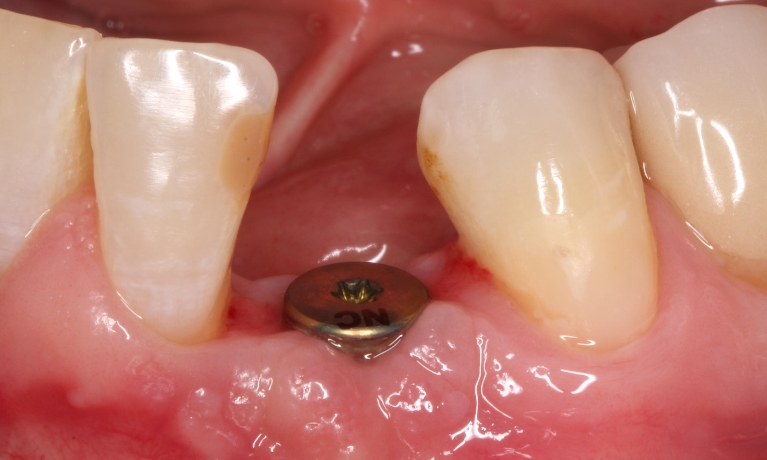

Stomatologiyanın təməl vəzifələrindən biri, itirilmiş dişlərin funksiya və estetik olaraq təbiiyə ən yaxın şəkildə bərpa edə bilməkdir. Dişsizliyin estetik və funksional olaraq yüksək səviyyədə reabilitasiyası, pasiyentlərin çeynəmə, danışma və gülmə kimi funksiyalarını qüsursuz icra edə bilməsi baxımından çox önəmlidir. Diş implantları xüsusi texnologiya hazırlanaraq, itirilmiş dişin bərpası üçün tətbiq edilən süni diş kökləridir. Bu metod təbiiyə ən yaxın bərpanı vəd edən müalicə metodu kimi uzun illərdən bəri beynəlxalq miqyasda geniş tətbiq olunur. İmplantasiya, bu işin peşəkarı yüksək ixtisaslı mütəxəssis tərəfindən qısa bir müddət davam edən prosedur vasitəsilə ağrısız, qısa müddətə və həyati funksiyaların məhdudlaşmaması şərti ilə həyata keçirilən müalicə üsuludur.

Dental implantlar əsasən titandan hazırlanır. Bu materialdan hazırlanmasının ən başlıca səbəbləri, bu metalın orqanizm tərəfindən rədd edilməməsi, heç bir allergik reaksiyaya səbəb olmaması və bu təyinat üçün yetərli möhkəmliyinin olmasıdır. Diş implantları vasitəsilə, tək diş əksikliyindən, çoxsaylı diş əksikliyi və tam dişsizlik halları funksional və estetik bərpa edilə bilir. İmplantın üzərinə hazırlanan diş konstruksiyaları müvafiq vəziyyətlərdə implantların tətbiqi ilə eyni gündə və ya müəyyən bir sağalma dövrünün keçməsindən sonra hazırlana bilir. İmplantların istismar müddəti, doğru planlama və icraat həyata keçirildiyində, eyni zamanda yetərli gigiyenik qulluq şəraitində bir neçə on illik bir periyodu əhatə edə bilir.